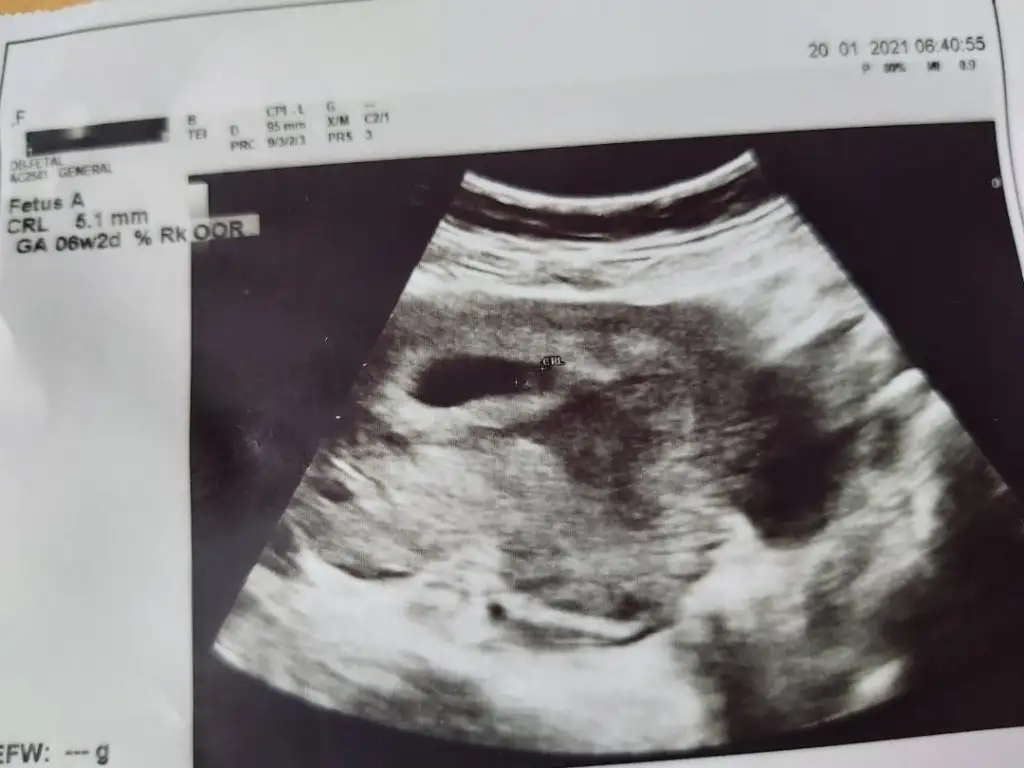

Ben de bugün kalp atışını duymadım ama gördüm pitpit benim hesabıma göre 6+5 ama doktor 6+2 dedi. Sormadım niye diye. Bir de dandik bir ultrason görüntumuz var, sol tarafta sağa yaslı gibi duruyor. Tahminen ne oluyor

Eklentiler

• thumbnail.webp

25,8 KB · Görüntüleme: 74